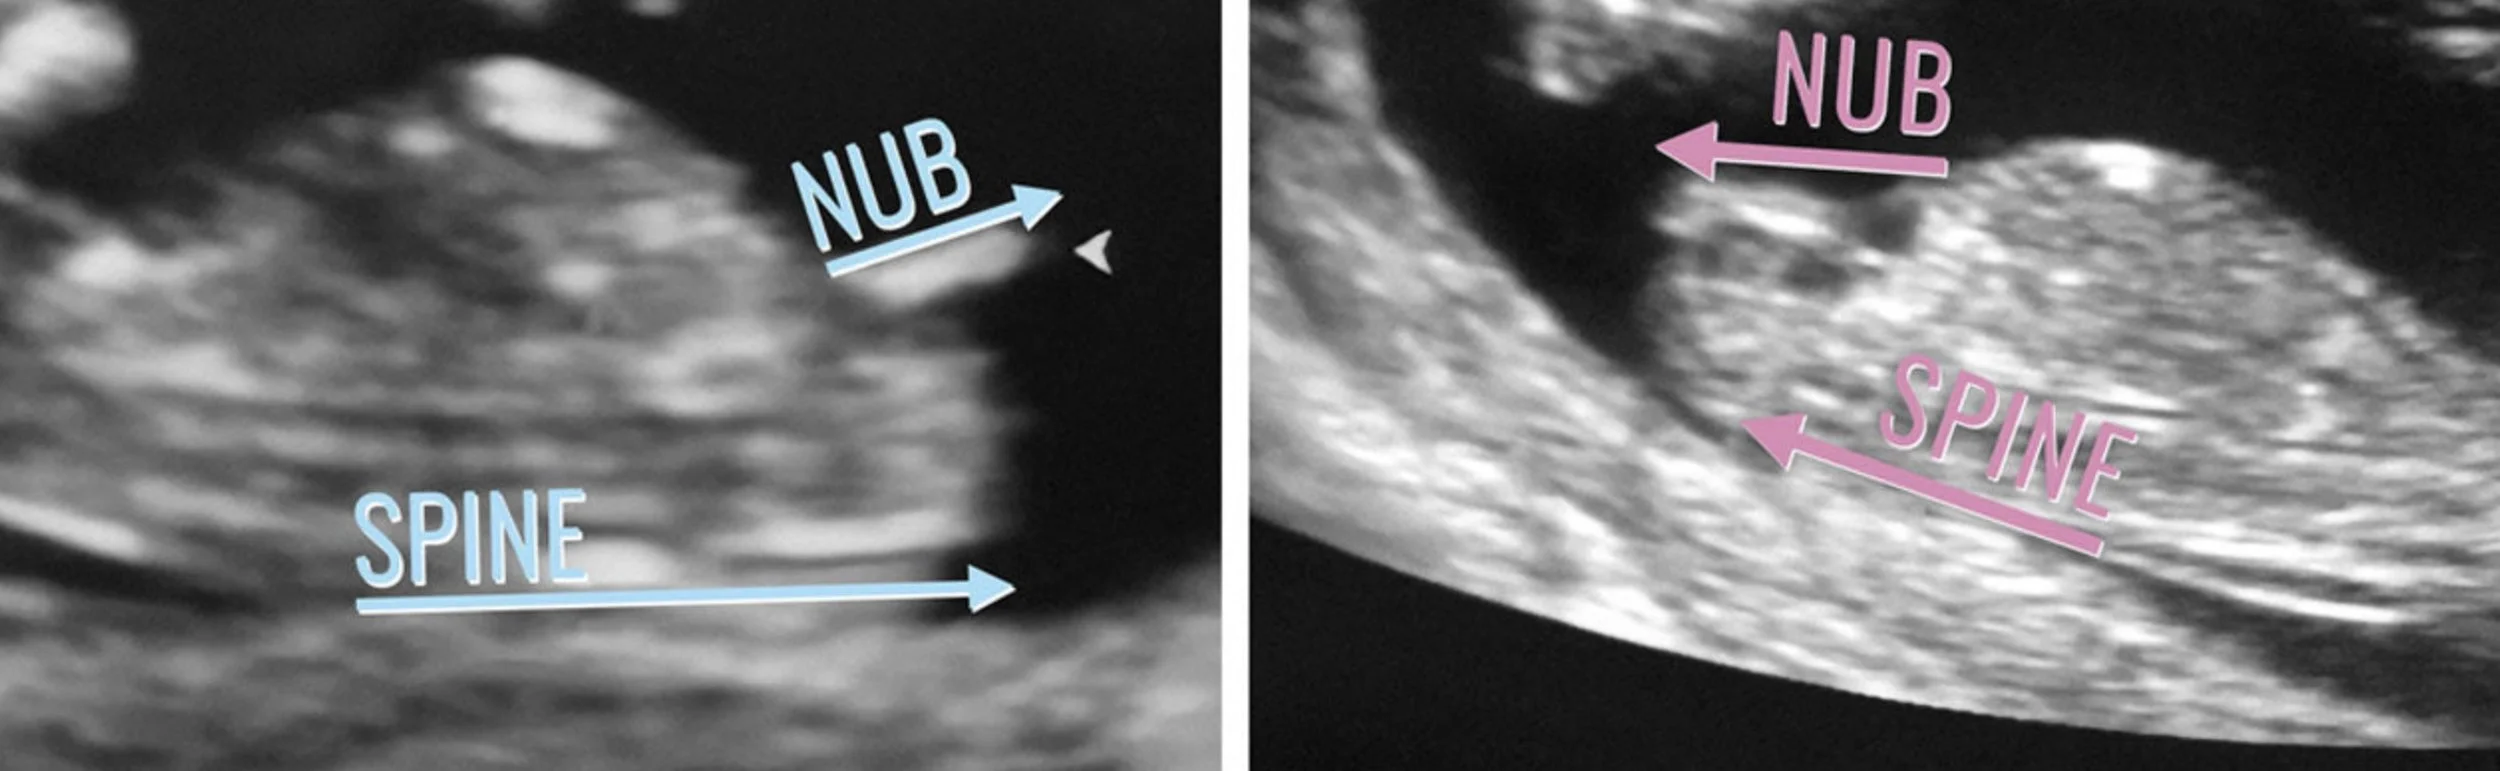

By looking closely at the angle of the nub in relation to your baby’s spine, experienced sonographers can often make an educated guess about your baby’s gender.

- 💗 If the nub is angled less than 30° from the spine, it’s likely a girl.

- 💙 If the nub is angled more than 30° upward, it’s likely a boy.

The angle of the nub for a boy and a girl.

But it’s not just about the angle, we also look at: